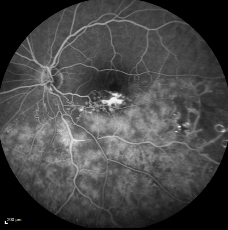

传统造影系统的荧光素钠血管造影 (FFA) RPE病变透亮区看不到细节

Spectralis HRA高清晰造影图像

传统造影系统的吲哚青绿血管造影 (ICGA) 中晚期造影图像缺乏对比度,无法分辨细节